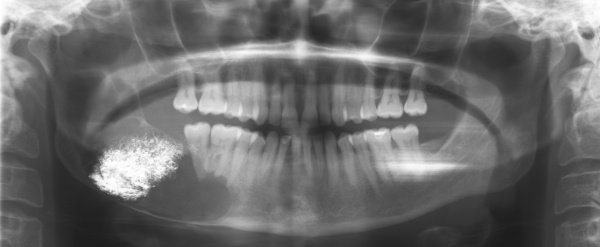

In einer extern angefertigten Panoramaschichtaufnahme bestand eine im Bereich apikal der Zähne 44-47 liegende und bis unterhalb des Processus condylaris reichende, ausgedehnte, mehrkammerige, scharf begrenzte Aufhellung. In direkter Lagebeziehung mit dem zystischen Prozess stellte sich apikal des Zahnes 46 der retinierte und verlagerte Zahn 45 dar.

Anamnestisch handelte es sich bei dieser Röntgenaufnahme um die erste Panoramaschichtaufnahme, die jemals bei dem Patienten angefertigt wurde (Abbildung 1).